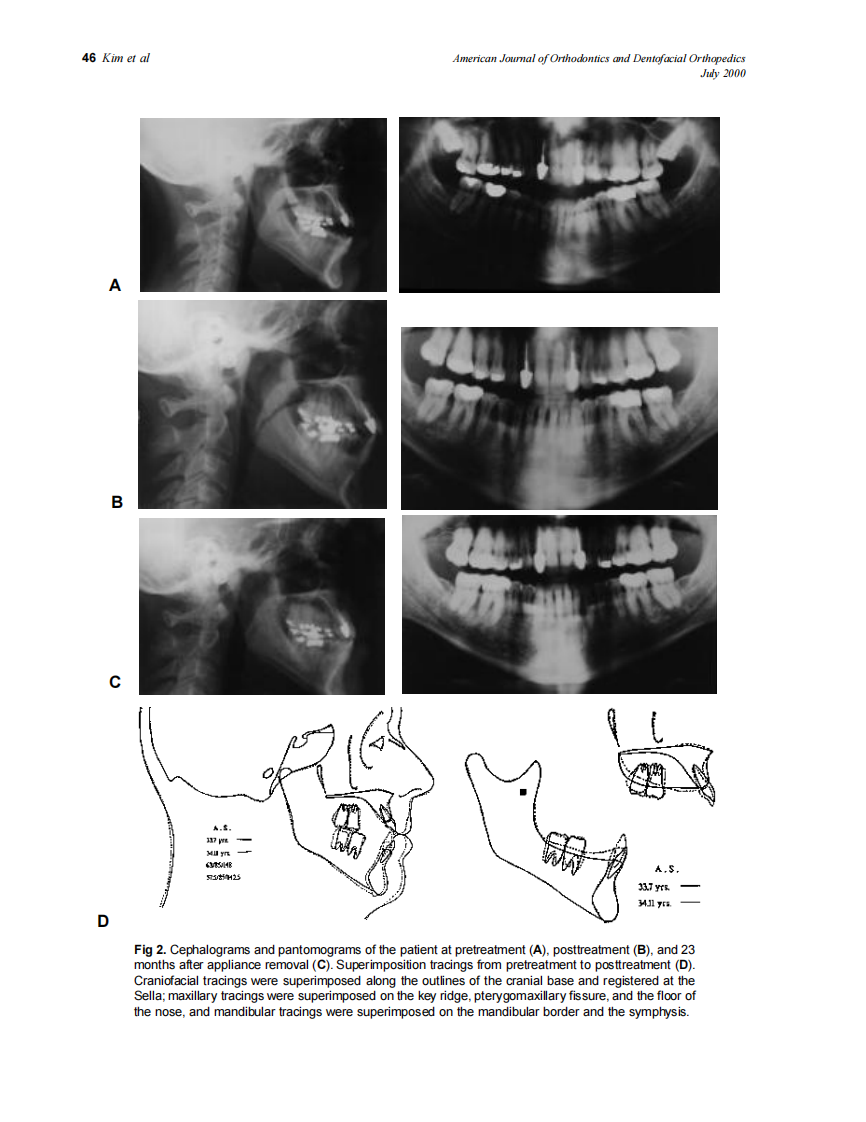

2000_118_1_43_54_Kim.pdf